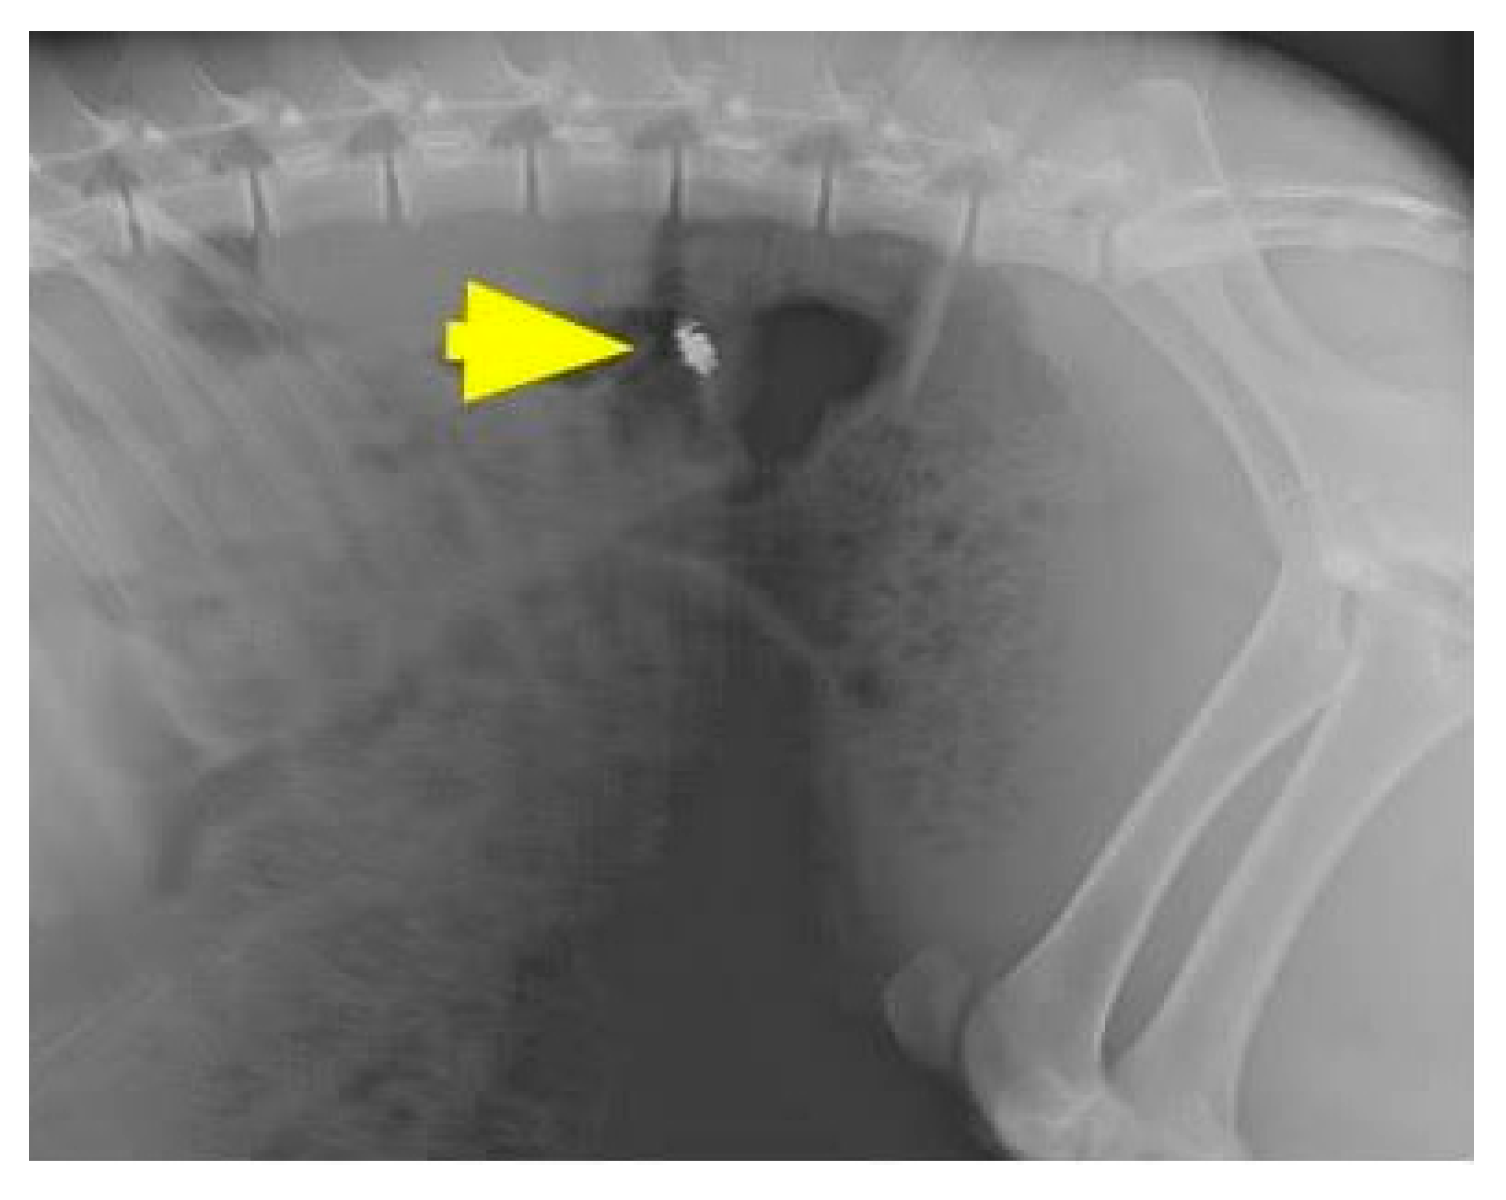

Pressure sensors (telemetric pressure probes and/or PDT) were inserted into each animal, as illustrated in Figure 3. Following the insertion of gastrointestinal intraluminal pressure (GIP)-sensing devices, herein called PDT, the animals were observed for 72 h to monitor for wireless sensor capsule operation, leakage, embolic events, or other adverse events as they related to the surgical procedure. The location of the wireless electronics was checked using fluoroscopy (Siemens Inc., Munich, Germany), as shown in Figure 4.

Figure 4.

The location of the ingestible capsule, PressureDot, was checked using fluoroscopy. Arrow: the ingestible capsule.